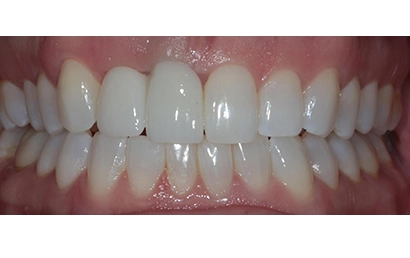

The fixed cantilever bridge was inserted, and seating was verified with a periapical X-ray. Torqued to 20 Ncm. Contacts were checked, and occlusion was adjusted. Final photographs and a scan were taken for the records.

Images were taken at the insertion appointment. Soft tissue healing remains ongoing.